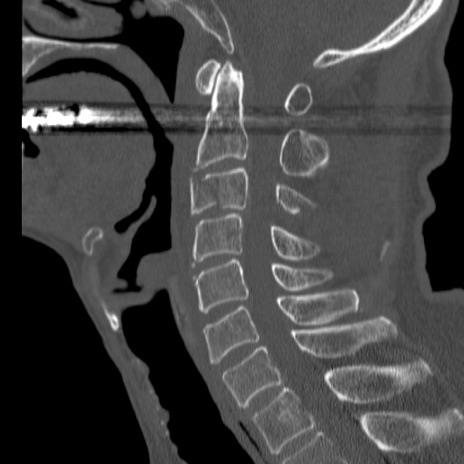

症例46 頚椎CT(矢状断像)

【症例】80歳代男性

【主訴】両側頚部〜上肢のしびれ

【現病歴】昨日、自宅内で転倒、その後より上記症状あり。意識障害なし。

【身体所見】両側上肢のallodynia(熱痛覚過敏)あり。MMTおよびDTRは正確な所見取れず。両上肢の挙上はなんとか可能。

異常所見と診断は?